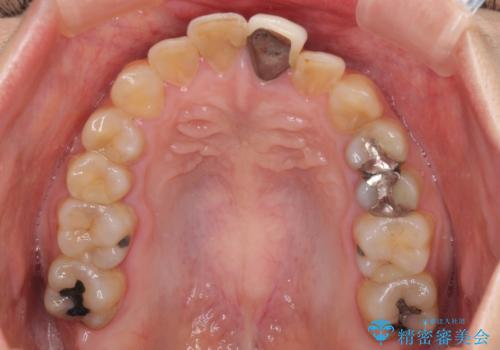

前歯のデコボコをワイヤー矯正できれいに整える

- 前歯のデコボコと変色した前歯を気にして来院された患者様です。

抜歯矯正により口元を引っ込めることも検討しましたが、特に口元の突出感は気になっていないとのことで、非抜歯にてワイヤー装置で矯正治療を行うこととしました。

気になっていた前歯の変色も、矯正治療後にオールセラミッククラウンにて補綴治療を行うこととしました。